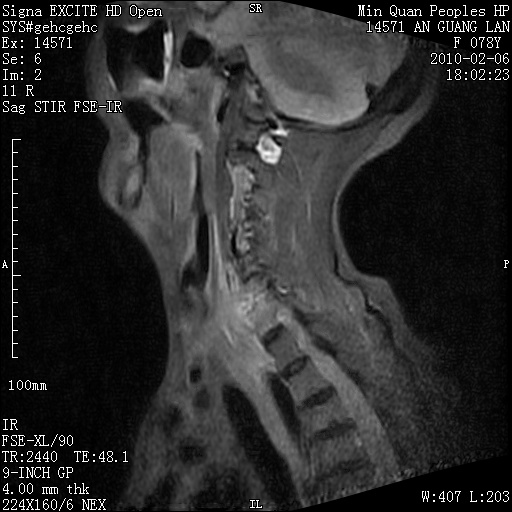

标题: MRI2763:C6、C7椎体病变性质?

f,78y,颈部与双上肢阵发性剧痛40余天。ct可见c6、c7椎体虫蚀样破坏,其间椎间隙变窄(没有图片资料可供上传)。